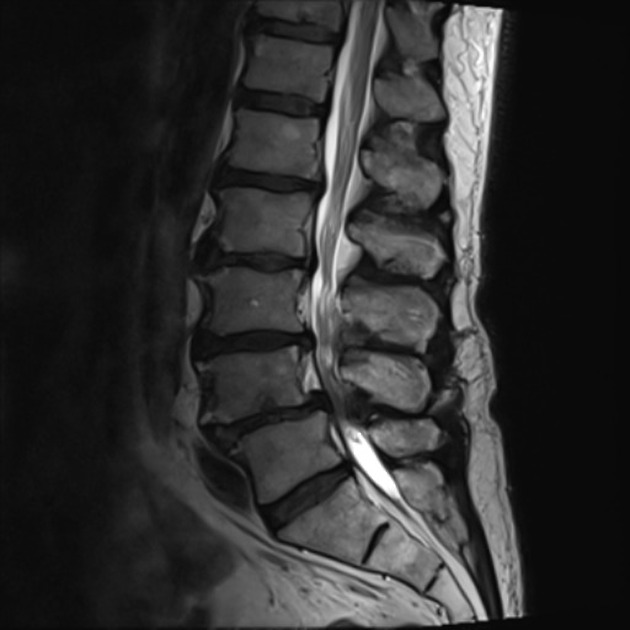

Photo Credit: radiopaedia.org

Interestingly, most of as we age accumulate changes in our spine including disc herniations, disc tears, and spinal stenosis yet we remain symptom free. MRI s in asymptomatic people continue to shown these changes due to the high sensitivity of this testing, but we given the high risk of false positives we must ask if these changes directly correlate with our symptoms. A recent review article in the journal Spine authors analyzed the available evidence to determine if MRI findings correlated with back or leg symptoms (Burgstaller et al. 2016). The authors reported that they “were not able to prove any correlation MRI findings and severity of pain”. This highlights the growing evidence behind the limitations of MRI findings to determine a patient’s symptoms, function, or prognosis.